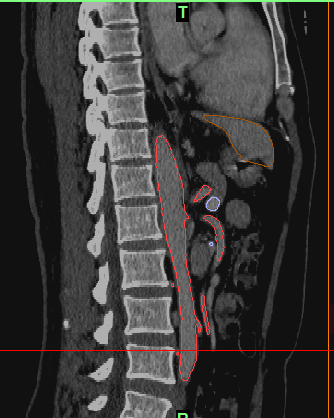

最后建模出来的效果:

三种视图: